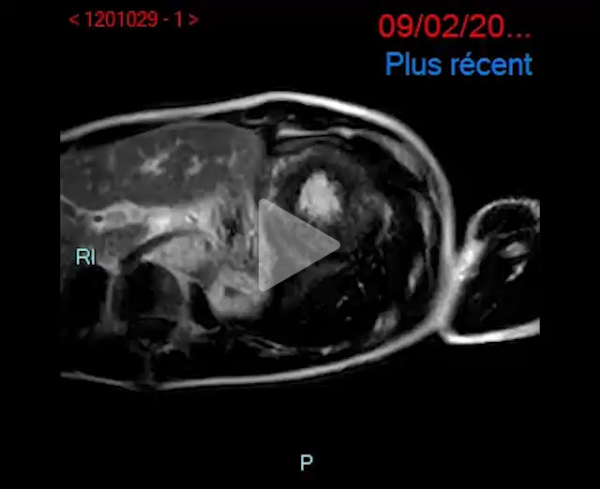

IRM cardiaque en février 2023 :

- Cardiomyopathie hypertrophique évoluée

- Dysfonction biventriculaire sévère, FEVG 19%, FEVD 22%

- VG dilaté

- IRM en faveur d'une pathologie de surcharge : pas d'argument pour un Fabry en IRM

- Faisceau d'arguments plutôt évocateur d'une amylose cardiaque

Vidéo 3